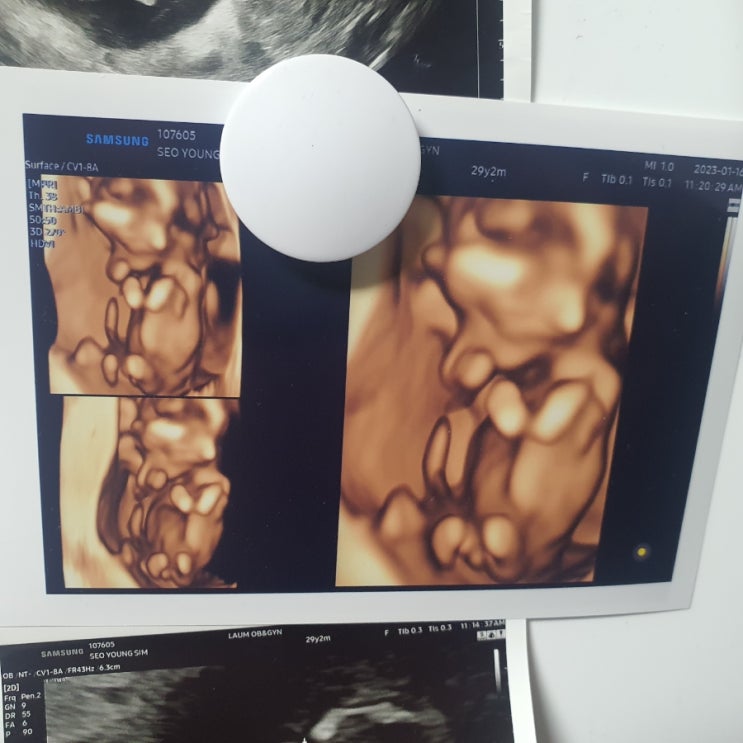

임신 20주~28주 / 비만산모 임당검사 통과, 아기성별 확정, 혼혈아기 입체초음파, 임신중 이사하기

19주 포스팅이 마지막 임신일기였는데 이걸 쓰는 지금은 34주...ㅋㅋㅋㅋ 입니다 임신 후기고 곧 아기를 만...